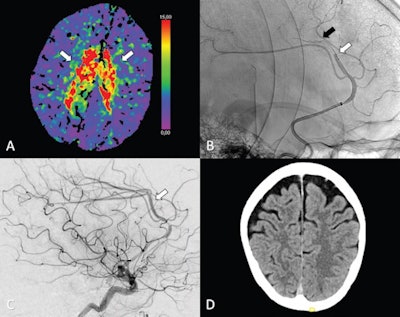

Mechanical thrombectomy is a type of minimally invasive endovascular therapy in which an interventional radiologist uses specialized equipment to remove a clot from a patient's artery. This restores blood flow and reduces damage to brain tissue.

While endovascular therapy has become the gold standard treatment for large vessel occlusion strokes, recent advances in technology have made the procedures possible in some of the brain's narrower vessels, as in distal medium vessel occlusions (DMVOs) of the anterior cerebral artery (ACA), the authors explained.

The analysis showed that thrombectomy was a safe and technically feasible option. Within the first 24 hours after treatment, thrombectomy patients had similar outcomes to those who received best medical treatment alone, with or without intravenous thrombolysis. In addition, thrombectomy for primary isolated occlusions led to high rates of successful reperfusion in 76 of 94 patients (81%), according to the findings.